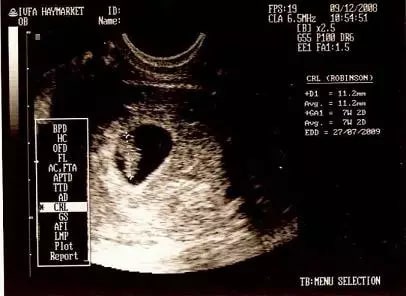

2、需要有孕囊的3個邊長數(shù)據(jù)

很多媽媽的B超單上只有兩個數(shù)據(jù),比如4.0cm*2.6cm,這只是橫截面的數(shù)據(jù),不能用來看男女,很多媽媽看錯就是這個原因。只有3個數(shù)的數(shù)據(jù)才能看,比如4.0cm*3.8cm*2.6cm。

根據(jù)前輩們的經(jīng)驗,長條形孕囊是男生,反映在數(shù)據(jù)上就是,其中兩條邊長要是第三條邊長的兩倍以上,比如4.0cm*3.8cm*1.9,這種兩條長邊接近,正好是第三條邊2倍的,是標(biāo)準(zhǔn)男寶。比如4.0com*3.2.com*1.2cm,這種一條邊特別短的80%是男寶。這些都可以想象出來因為有一條邊特別短,所以孕囊肯定是細(xì)長型的。

圓形孕囊是女生,反映在數(shù)據(jù)上就是,三條邊長差不多,或三條邊長成等差數(shù)列,長邊沒有短邊兩倍的,比如4.0cm*3.3cm*2.7cm或2.9cm*1.8cm*1.8cm,這些都是女孩。

有的人數(shù)據(jù)是2.7*3.6*1.8,第一個數(shù)字不是最大值怎么看,沒關(guān)系,按照從高到低再排列成3.6*2.7*1.8這樣看就行。當(dāng)然也有一些媽媽的數(shù)值不是很明顯符合以上特征的,那就是男女都有幾率了。